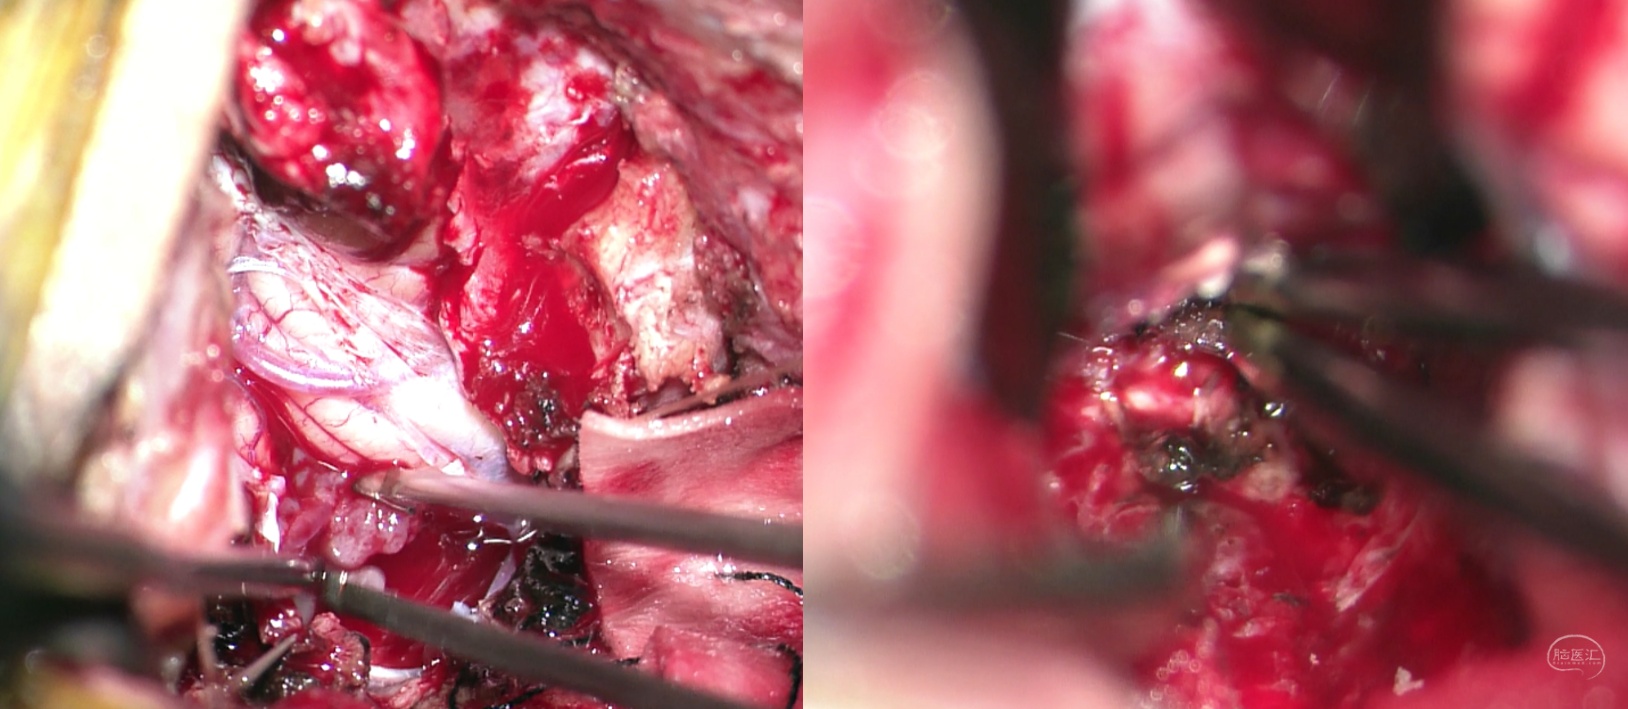

术中打开后枕部骨窗,打开枕大池,C1未去除,充分暴露,游离蛛网膜,牵开小脑扁桃体,暴露肿瘤,分块切除,分离切除过程中注意四脑室底保护,分离后及时棉片覆盖,避免损伤。脑干面少许渗血可采用压迫、流体明胶等方式止血,减少电凝损伤。